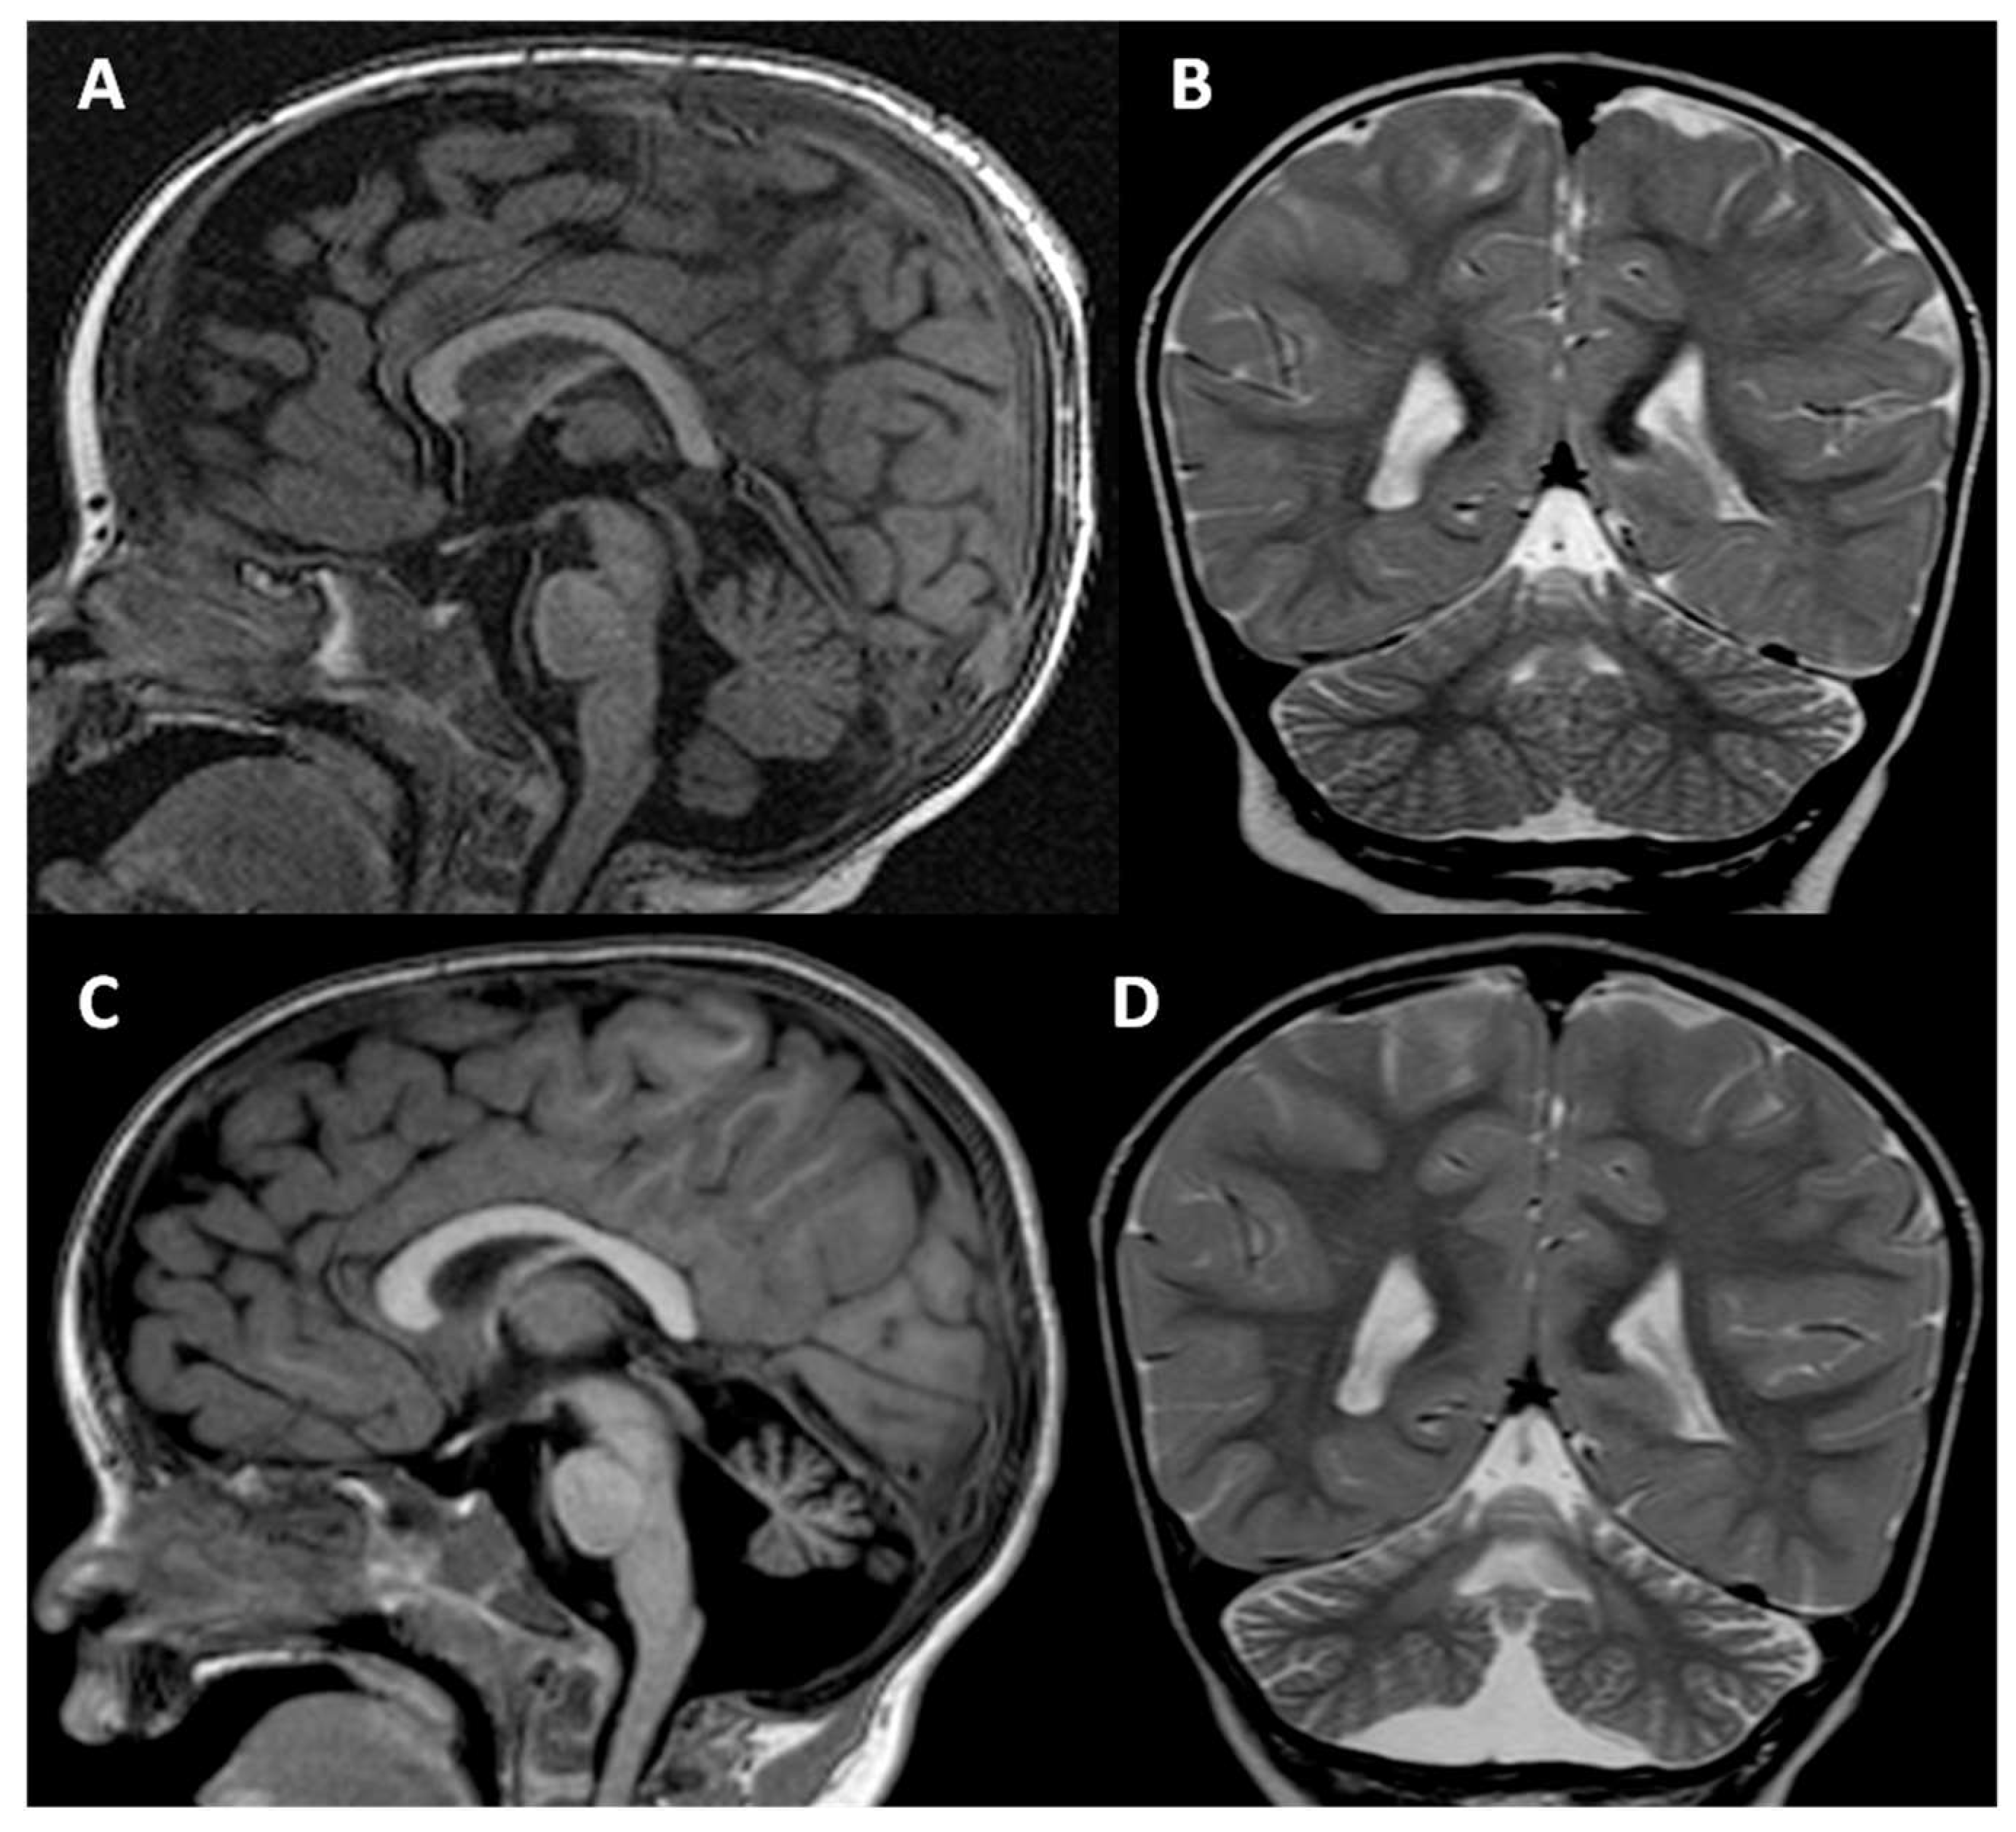

When the patient was 31 months old, he developed seizures, which were treated and controlled with levetiracetam. Two MRI scans of the brain, which the patient underwent when he was 3 months and 3 years old, showed progressive atrophy of the whole cerebellum, but especially of the vermis, with increased pathological and symmetrical hyperintensity on T2-weighted images of the dentate nuclei. The corpus callosum was normal except for minimal hypoplasia of the rostrum. The brainstem remained normal in both MRIs. The second MRI showed the appearance in the deep left temporal white matter of an oval-shaped area, hyperintense on T2-weighted images, about 1 cm in size, without peripheral vasogenic edema an enhancement after gadolinium injection, currently under follow-up (Figure 2).

Figure 2.

MRI of the brain was performed when the patient was 3 months (A,B) and 3 years old (C,D). Both midline sagittal T1-weighted and coronal T2-weighted images demonstrate a progressive reduction in cerebellar volume, especially of the vermis, with diffuse atrophy of the folia and secondary enlargement of the subtentorial CSF spaces. The corpus callosum is normal except for minimal hypoplasia of the rostrum (A,C). Note also the pathological progressive increased hyperintensity on T2-weighted images of the dentate nuclei (B,D).